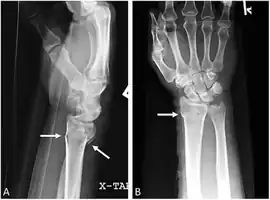

| Galeazzi fracture | Ricardo Galeazzi | radius shaft fracture with dislocation of distal radioulnar joint | blow to forearm | Galeazzi fracture Archived 2017-12-01 at the Wayback Machine at eMedicine |